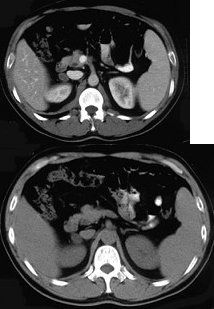

女,23岁,满月脸、向心性肥胖,CT扫描如图所示,应诊断为( )

A:右侧肾上腺增生

B:右侧肾上腺腺瘤

C:右侧肾上腺腺癌

D:右侧肾上腺嗜铬细胞瘤

E:右侧肾上腺转移瘤